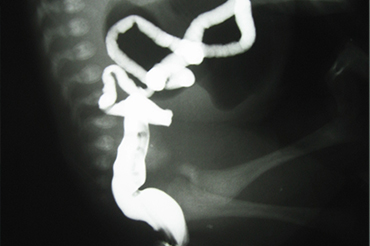

Atresia Intestinal

Inicio Neonatal y Lactante

Neo Natal y Lactante